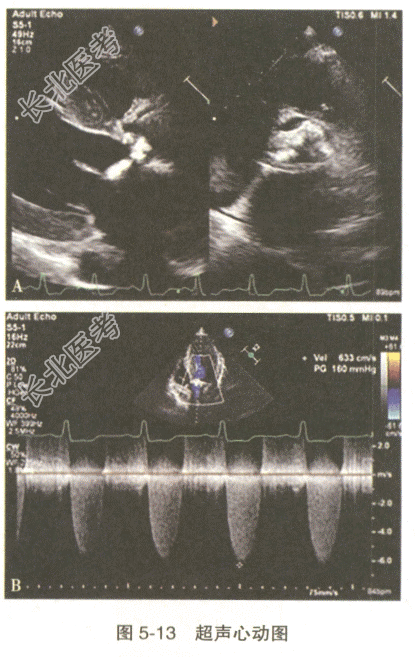

- [材料题] 患者,男性,75岁。因“胸闷、气促数年,加重1个月余”入院,查体:生命体征平稳;心脏听诊可于主动脉瓣区闻及4/6级收缩期粗糙高音调的喷射样杂音;心电图提示左心室高电压、左心室肥厚、T波倒置;胸部X线片提示左心缘圆隆,左心房增大,肺动脉主干突出,肺淤血;心脏彩超检查见图5-13,提示主动脉瓣大量钙化斑,主动脉瓣瓣口收缩期射流加速,舒张期瓣口未见明显反流信号。

- 多项选择题2.此患者主动脉瓣口收缩期射流峰速6.3m/s,压差160mmHg。以下叙述准确的是